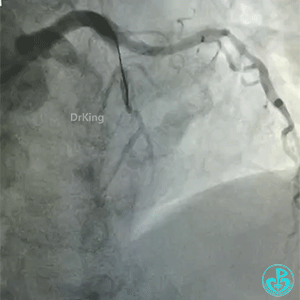

急性前壁心梗,两小时。

导丝怎么扩真怪!急性心梗前降支导丝通过顺利,球囊扩张后导丝移位很多!不在原来的血管腔!

怎么解释导丝和血管的关系?

BMW导丝,预扩前导丝是弯曲的,预扩时球囊也是弯曲的,预扩后导丝拉直,血管的弯曲还在。